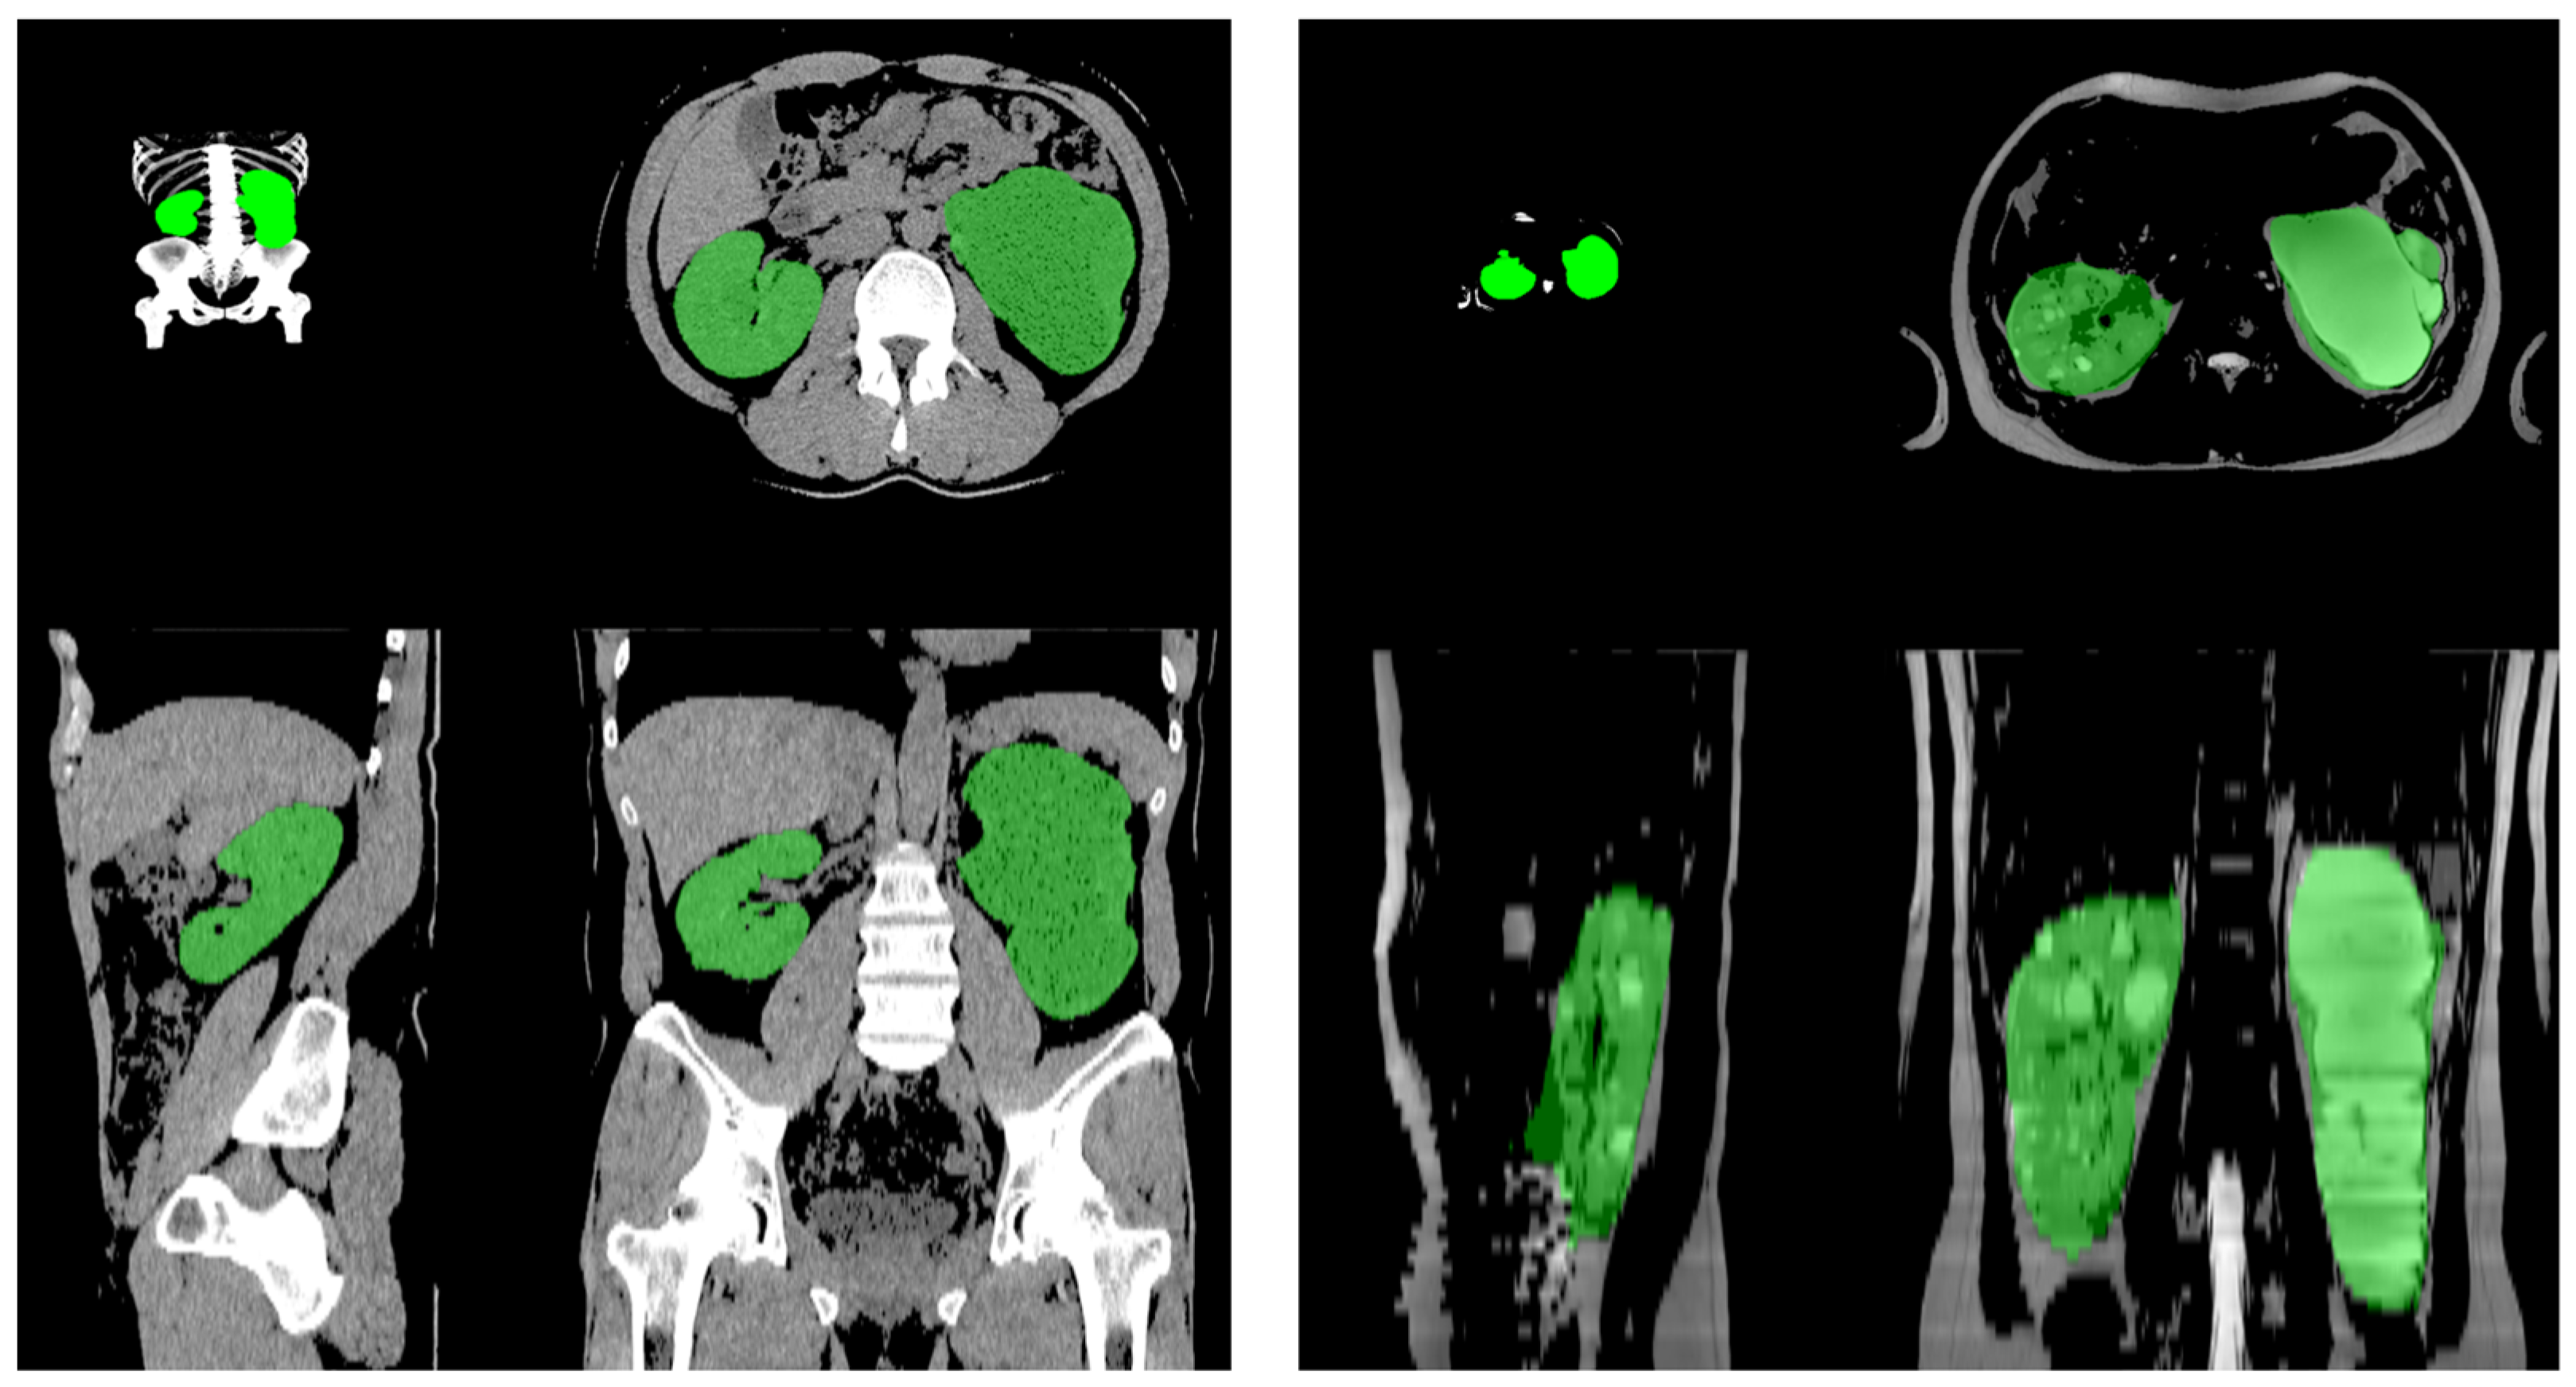

Comparison Between the Human-Sourced Ellipsoid Method and Kidney Volumetry Using Artificial Intelligence in Polycystic Kidney Disease

2. Methods